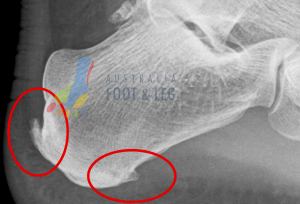

The Calf Muscle Attachment (Posterior Heel Spur):

- The number one muscle that is tight in at least 95% (anecdotal figure) of patients is the calf muscle. As a result on imaging we can typically see spurring, or at least excess bone deposit at the rear of the heel where your achilles tendon attaches to the heel bone. You can find an example of this shown on the foot x-ray below highlighted by the red circle.

The Arch Muscle Attachment (Plantar Heel Spur):

- the next common muscles that are tight in many patients experiencing heel pain are the arch muscles. Please be aware there are multiple arch muscles in the foot – here we’re over-simplifying the topic for ease of illustration but many share a similar attachment point at the bottom of the heel bone. You can find an example of this shown on the foot x-ray below highlighted by the red circle.

The Arch Ligament Attachment (Plantar Fascial Heel Spur):

- the final point that is rarely seen by itself but still worth a mention as it is a sign of long-standing plantar fascia attachment irritation of the heel bone is what we call the plantar fascial heel spur. This attachment point is the true attachment of the plantar fascia and irritation here is a sign of excessive strain through the plantar fascia. Bear in mind your plantar fascia is a strong ligament (bone to bone not muscle to bone with a tendon) so when this is pulling excessively your foot muscles have ‘given up’. You can find an example of this shown on the foot x-ray below highlighted by the arrow pointing at the red circle.